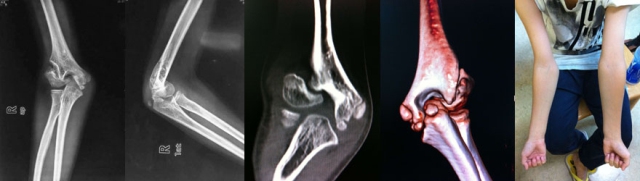

学生:12岁男孩,2岁时有外伤史,无原始片。因右肘外翻和提重物力量差就诊,体格检查右肘关节屈伸功能良好,没有神经受累症状。您的诊断?

老师:我考虑有两种可能,既往发生过肱骨外髁骨折或者肱骨远端全骨骺分离。两者的一个重要区别点就是是否存在外翻不稳定。如有明显的外翻不稳定,则多数情况下应该是陈旧外髁骨折。如果只有外观外翻而没有外翻不稳定,则有可能是很小时候发生的肱骨远端全骺分离长期塑形的结果,也有不愈合的可能,但后者可能性很小,陈旧外髁骨折的可能性大。